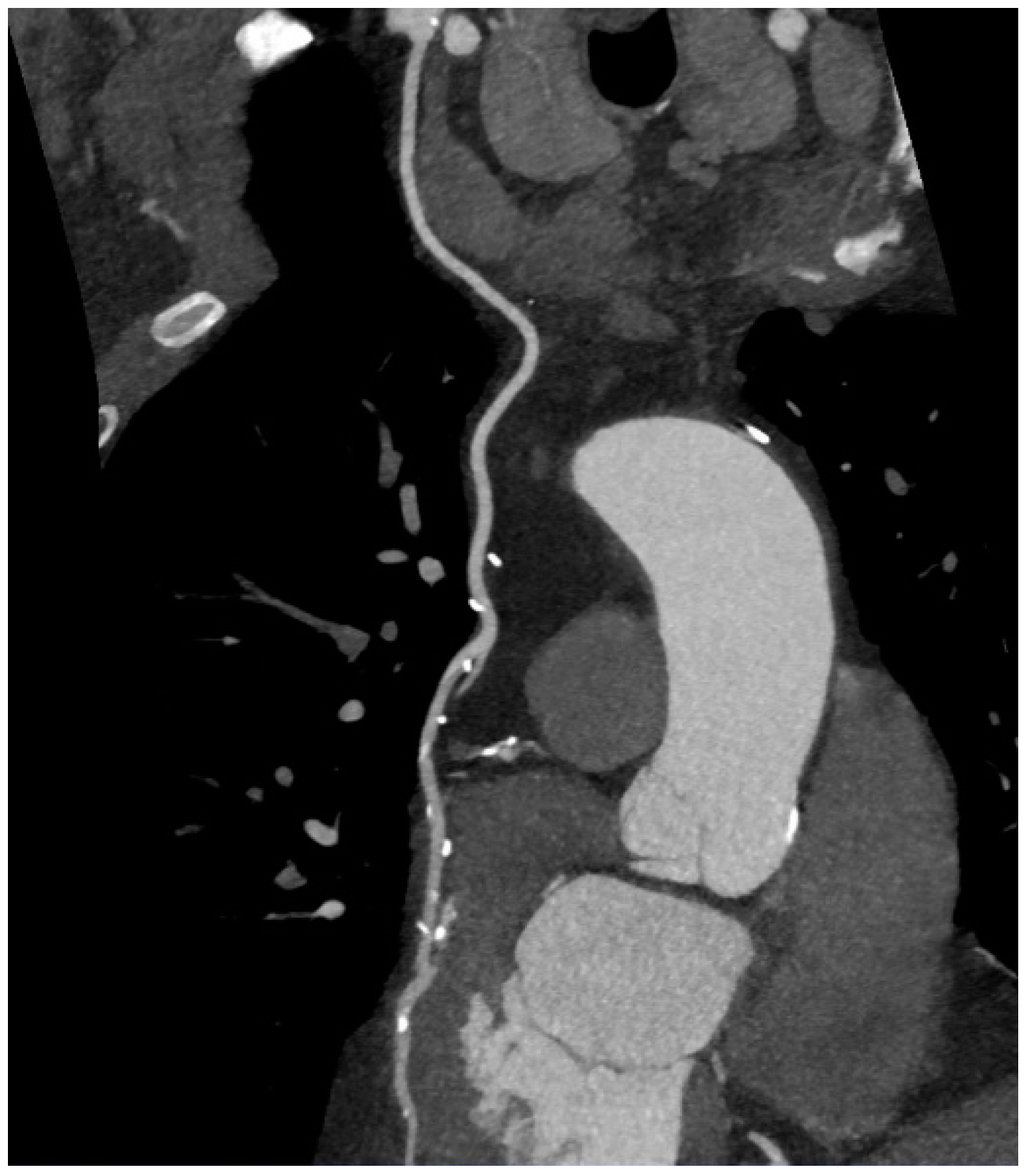

5. Coronary CT Angiography

6. Imaging of Coronary Plaques and Stenoses